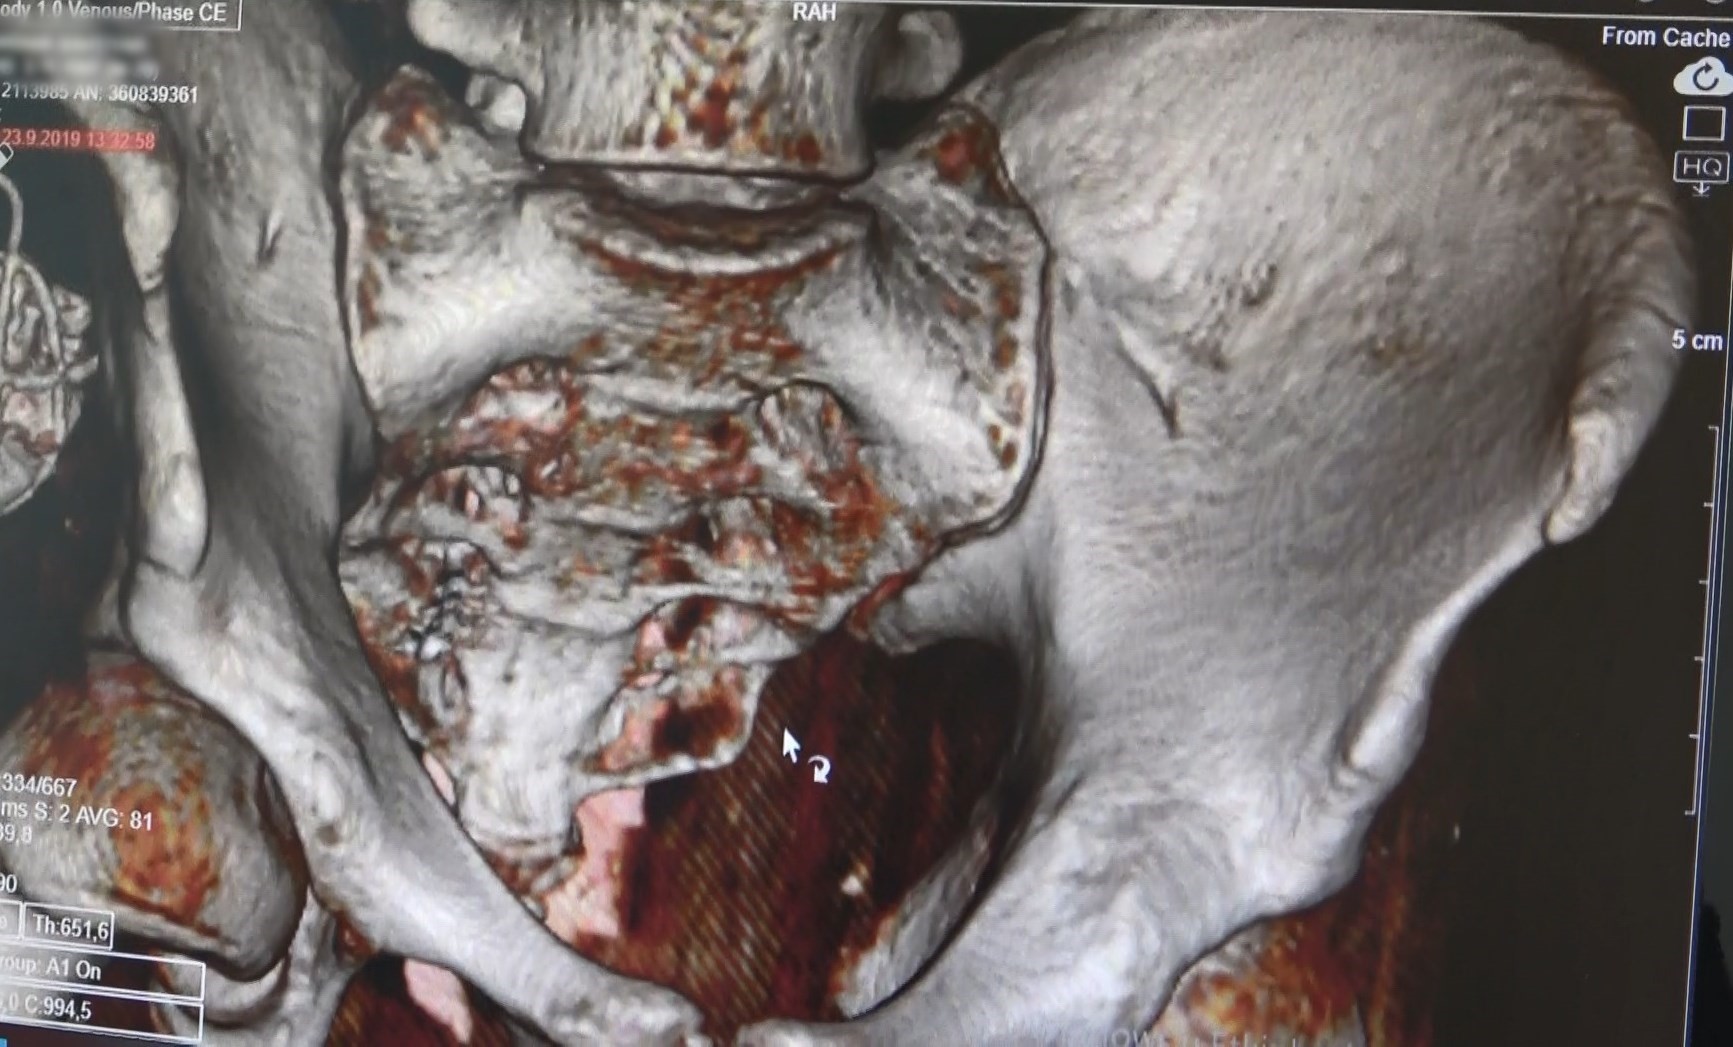

Mesane Pili ile ilgili açıklamalarda bulunan Üroloji Uzm. Doç. Dr. Kadir Önem, “Mesane pili terminolojide ‘sakral nöromodulasyon' olarak geçer. Mesaneye giden sinirleri uyarmak için yaptığımız bir tedavi yöntemidir. Mesane pili dediğimiz bu tedavi yöntemi 3 hastalığın tedavisi için kullanılır. Biz idrar kaçırmada ilk önce ağızdan alınan ilaçlar veriyoruz hastalara, ikinci aşamada ağızdan alınan ilaçlar fayda etmediyse mesaneye botoks yapıyoruz. Üçüncü aşamada da mesanenin, mesanenin sinirlerini uyaran mesane pili uygulamasını yapıyoruz. İkinci kullandığımız hasta grubu idrar yapamayan, idrar yapması için temiz aralıklı kateterizasyon(TAK) dediğimiz bir yöntem var TAK veya CIC dediğimiz. Hastalar bu ‘kateterle' günde 4 sefer ya da 6 sefer kendi idrar yollarına takarak mesaneyi boşaltırlar. Eğer hasta bundan kurtulmak istiyorsa belli bir seçilmiş grupları bütün hastalar değil o zaman mesane pili önerebiliyoruz. Mesane pili taktıktan sonra bu sistemi yeniden regüle ediliyor. Mesane pili refleksleri yeniden düzenliyor. Hasta idrarını tekrar yapmaya başlayabiliyor. Üçüncü dediğimiz hasta grubu ise ağrılı mesane sendromu dediğimiz hastalardır. Bunlarda da idrarını yapsın ya da yapmasın her an ağrı oluşan mesanesinde bacak arasına doğru ağrı yayılan ya da suprapubik bölge dediğimiz karnın alt kısmına doğru ağrı yayılan, mesaneden kaynaklanan bir ağrı sendromudur. Dünya genelinde birçok tedaviler denenmiştir. Bunlardan bir tanesi de mesane pilidir. Bu da ağrılı mesane sendromlu hastalarda sık sık tuvalete çıkmayı mesanede oluşan ağrıyı azaltmaya yönelik tedavi hedeflerimiz vardır. Bunlarda da mesane pili etkin bir tedavi yöntemidir. Tabii tüm hastalar da değil ortalama başarı oranları var bunlarda da en düşük ağrılı mesane sendromunda daha az yanıt alıyoruz. Evet, yanıt belki yüzde 50'den fazla alıyoruz ama diğer gruplara göre birazcık daha düşük bir oranda yanıt aldığımızı söyleyebilirim. İdrar yapmayan hastalarda ya da idrar kaçırması olan hastalarda gayet iyi oranda yanıt aldığımızı belirtmek isterim” diye konuştu.

"Sigorta ya da devlet kurumlarının ödemesinin olması ya da olmaması da etkili bir faktördür. Yaş grubu olarak aslında çocukluk yaş grubundan, yaşlılığa kadar her yaş grubunda kullanabileceğimiz bir tedavi yöntemidir. Şimdiye kadar sanırım en küçük yaş 9 yaşındaki bir hastamıza takmıştık. Erzurum'dan gelen, yaşlı olarak ise 65 yaşında bir hastama da taktığımı hatırlıyorum üst limit olarak. Dördüncü grubumuz ise tabi Türkiye'de şu anda özel sigortalar hariç SGK'nın ödemesi kapsamında idrar kaçırma, mesane sendromu ve idrar yapamama durumlarında SGK tarafından karşılanıyor. Örneğin; bir trafik kazası geçirdi hasta idrar yapamıyor ya da idrar kaçırması var bu grup hastalarda mesane pili kullanabiliyoruz ki bunlar da erken yapılan mesane pillerinde mesanenin uzun dönemde daha iyi korunduğuna dair veriler de yakın zamanda yayınlandı. Nörojen grubu hastalarda da mesane pili öneriyoruz. Cilt altında hissedebilir hasta pili tabi pillerin artık biraz daha ufakları, şarj edilebilirler, MR uyumlu olan formları piyasa sürüldü bunları kullanabiliriz. Eski piller bir parça büyük yeni piller biraz daha küçük. Bazen hastalara kart veriyoruz güvenlikten geçerken cihazlardan hafif bir elektrik çarpması hissedebiliyor hastalar havaalanlarına girerken, alışveriş merkezlerine girerken o yüzden bir kart veriyoruz hastanın üzerinde elektronik bir cihaz olduğuna dair onlardan geçmeyebiliyorlar. Onun dışında voltajı çok yüksekse bir ağrı hissedebiliyor zaten voltajını hastanın rahatsız olmayacağı en yüksek oranda ve fayda sağlayacağı bir oranda tutmaya çalışıyoruz. Şarj edilebilir piller 15 yıla kadar gidebiliyor, şarj edilmeyen piller de genelde voltaja bağlı olarak 4 ya da 5 yılda bir değiştirilebiliyor. Türkiye'de bazı olmazsa olmazlar var. Özel sigortalar değil de SGK'da mesela aşırı ağrılı mesaneden örnek verecek olursak önce botulinum toksin enjeksiyonu yapılsın ondan sonra fayda görmezse sakral nöromudasyon geçilsin diyor. Fakat yabancı ülkeler de mesela hap kullandı hasta faydası olmadı, o zaman botoks mu ya da nöromodülasyon mu diye hastaya sorulabiliyor. Yani botulinum toksin yapılması olmazsa olmaz olmayabiliyor. İkinci sırada kullanılabiliyor. Türkiye'de bir parça daha farklı önce botulinum toksin yapılsın ondan sonra nöromodülasyona geçelim denilebiliyor. Aslında uygun her hastaya kullanabiliyor. Buna da tabi hastanın hekiminin karar vermesi gerekiyor" şeklinde konuştu.